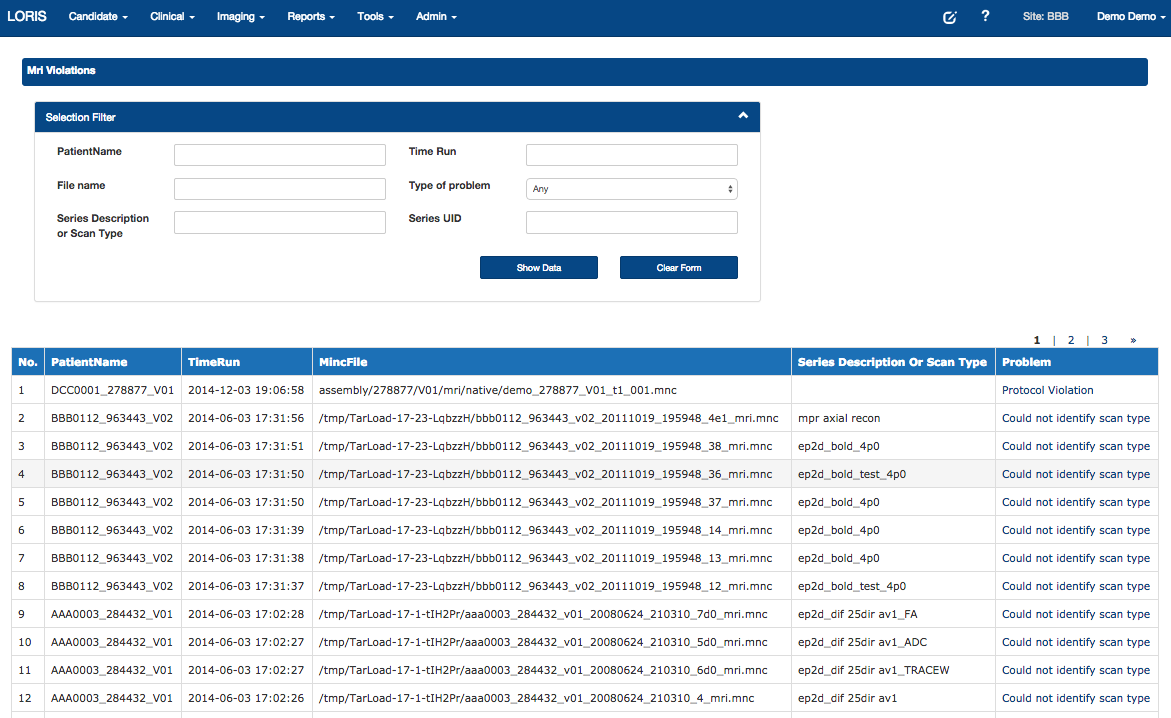

Protocol Violations

- Quality Control - Protocol violations, artefact detector, inter-rater reliability

Interactive Protocol Violations - New